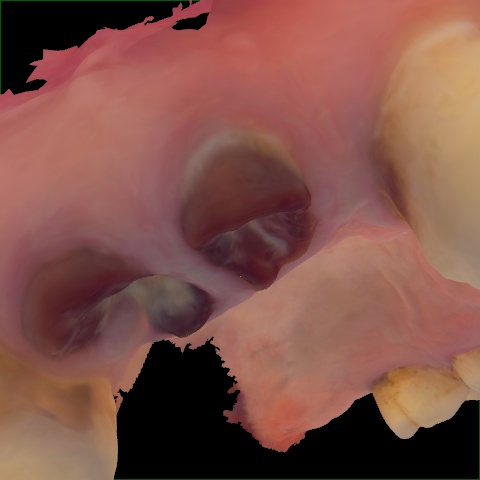

Image 1408 / 1743

NHD36692

Annotated as "Good"

Original Image Rendering Image